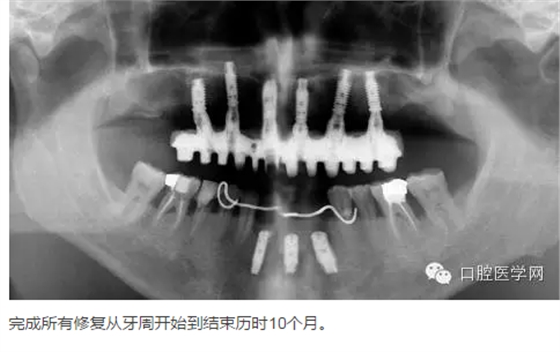

上頜牙全拔除進行上頜ALL-ON- 6導(dǎo)航手術(shù)即刻種植即刻負(fù)重骨支持式導(dǎo)板,我們的要求為扭力大于等于35N ISQ值大于等于70直徑大于等于4長度大于等于11.5 數(shù)量大于等于4。

下頜32到42 區(qū)域擇期進行即刻種植,植入三顆種植體后,常規(guī)活動臨時修復(fù)。

下頜45位置即刻種植不需要臨時修復(fù)。

轉(zhuǎn):口腔醫(yī)學(xué)網(wǎng)